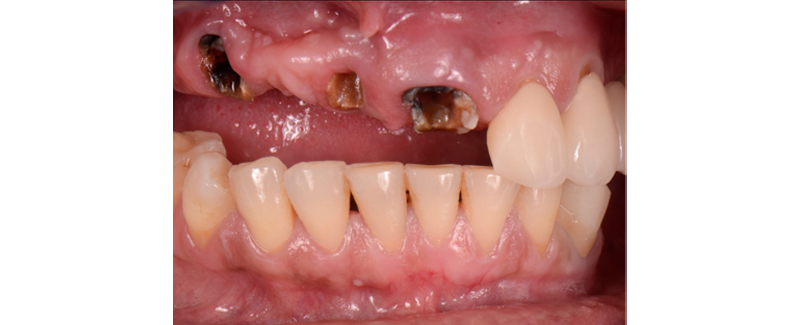

1. Advanced structural damage (Fig. 1)

2. Advanced periodontal damage. (Fig. 2)